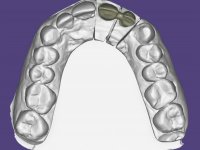

B – Plano de Tratamento Cirúrgico: Confeção de Ponte provisória de 2 elementos aderida aos dentes 1.1 e 1.2 e 2.3. Extração dos dentes 2.1 e 2.2 e colocação imediata de um implante no local do 2.1. Regeneração tecidular guiada no local a intervir. Ponte provisória de 2 elementos aparafusada sobre o implante. Ponte definitiva com infraestrutura em Zr revestida com cerâmica aparafusada com interface metálico ao implante.

Foi feito o tratamento endodôntico dos dentes 2.1 e 2.2.de imediato, a sintomatologia que o paciente manifestava a isso impunha. Na mesma consulta foi realizada uma extensa gengivetomia com o bisturi elétrico, no sentido de expor os limites cervicais da fratura. Foram colocadas resinas compostas nos remanescentes radiculares com a intenção de reformular a emergência dos tecidos moles. Realizei a impressão dos remanescentes radiculares para confeção em laboratório de uma ponte provisória. A ponte provisória de 2 elementos, apresentava um formato que visava no futuro acomodar o coto dos espigões falsos cotos que iria ser cimentados nos remanescentes radiculares. Apresentava um reforço metálico palatino e dois apoios para os dentes adjacentes, um mesial e outro distal. Os remanescentes radiculares foram preparados para a confeção de dois espigões falso coto fundidos. As linhas de acabamento cervical foram definidas e os canais radiculares desobturados e preparados. A impressão foi realizada com a utilização de tutores de plástico com a técnica de dupla mistura. O afastamento gengival foi feito utilizando pasta de caolino. A ponte provisória foi rebasada em boca com acrílico auto polimerizavel, cimentada provisoriamente sobre as raízes e os apoios colados aos dentes adjacentes. No laboratório foram confecionados os E.F.C. fundidos, tendo o cuidado de preservar espaço para a definição no re preparo dentário da linha de acabamento cervical. Removida a ponte provisória foi feita a cimentação dos E.F.C. fundidos com cimento de ionómero de vidro reforçado com resina. A ponte provisória teve que ser retocada para permitir a acomodação dos cotos e simultaneamente foi readaptada à redefinida linha de acabamento cervical. Durante 2 meses a ponte provisória acompanhou a estabilização periodontal das raízes traumatizadas e simultaneamente conseguiu a maturação da arquitetura gengival.